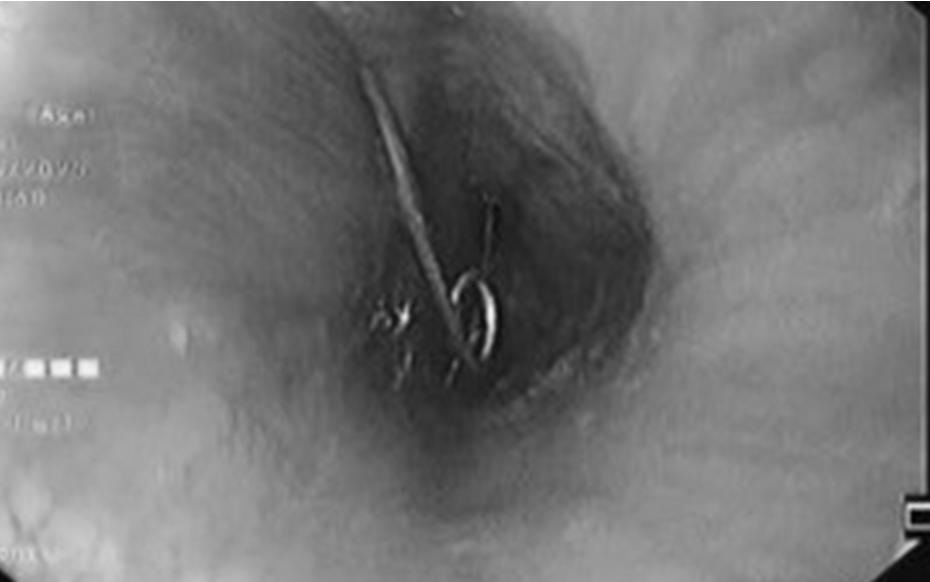

Cháu bé 1 tuổi nuốt kim băng đã bung đầu nhọn ghim vào thành thực quản. Ảnh: Bệnh viện cung cấp.

Tại khoa Cấp cứu, các bác sĩ tiến hành thăm khám và nội soi khẩn cấp. Kết quả cho thấy cây kim băng đã bung ra hình chữ L, đầu nhọn ghim vào thành thực quản gây nguy cơ thủng, xuất huyết và nhiễm trùng nặng. Đây là tình huống đòi hỏi xử lý nhanh chóng, chính xác và cẩn trọng để bảo vệ tính mạng và sức khỏe của bệnh nhi.

Tiếp đó, ê-kíp liên chuyên khoa gồm Tiêu hóa - Tai Mũi Họng - Ngoại khoa, Bệnh viện Nhi đồng 2 TpHCM được huy động để hội chẩn và triển khai phương án can thiệp. Sau quá trình xử lý nội soi tỉ mỉ, các bác sĩ đã lấy được dị vật mà không cần phẫu thuật mở. Nhờ sự phối hợp nhịp nhàng giữa các chuyên khoa, ca cấp cứu đã diễn ra an toàn, bé được cứu khỏi một tình huống nguy hiểm.